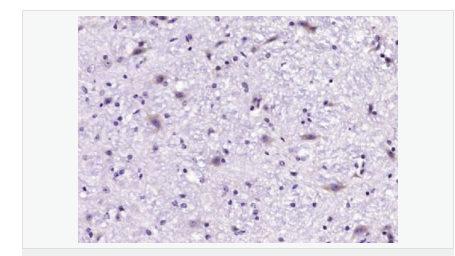

產(chǎn)品介紹GLRB (Glycine receptor beta) is a neurotransmitter-gated ion channel concentrated within the spinal cord and brainstem. Expression is also observed in several upper brain regions including the cortex, cerebellum, hippocampus and amygdala. Binding of glycine to GLRB increases the chloride conductance and thus produces hyperpolarization (inhibition of neuronal firing), controlling spinal reflexes and locomotor behavior.

The glycine receptor is a neurotransmitter-gated ion channel. Binding of glycine to its receptor increases the chloride conductance and thus produces hyperpolarization (inhibition of neuronal firing).

Pentamer composed of alpha and beta subunits. Interacts with GPHN

Plasma membrane; multi-pass membrane protein.

Defects in GLRB are the cause of hyperekplexia type 2 (HKPX2) [MIM:614619]. HKPX2 is a neurologic disorder characterized by muscular rigidity of central nervous system origin, particularly in the neonatal period, and by an exaggerated startle response to unexpected acoustic or tactile2 stimuli.

Belongs to the ligand-gated ion channel (TC 1.A.9) family. Glycine receptor (TC 1.A.9.3) subfamily. GLRB sub-subfamily.